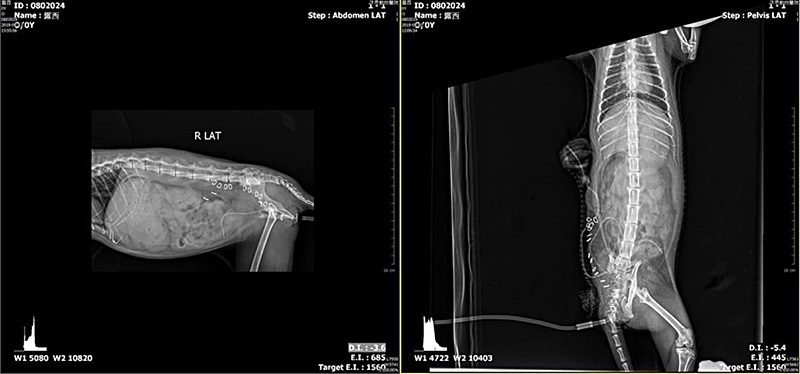

露西的泌尿道感染非常嚴重,經過月餘用藥治療,轉況才稍微好轉,又因有骨盆腔骨折影響排便問題,

再至長青進行電腦斷層診斷,以利泌尿道專科醫師進行股盆腔手術。

露西已確定是終身癱瘓、每日須人工擠便尿,並進行骨盆腔擴張手術,才能維持生活品質並以利後續照顧。